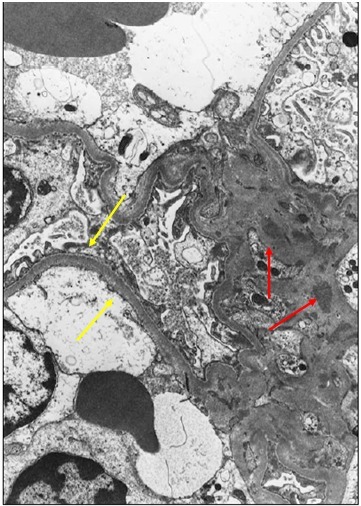

3. 电镜表现:

图 24 红色箭头:肾小球内皮细胞下大量电子致密物沉积;黄色箭头:肾小球系膜区电子致密物沉积

图 25 黄色箭头:肾小球内皮细胞下电子致密物沉积;红色箭头:肾小球系膜区电子致密物沉积